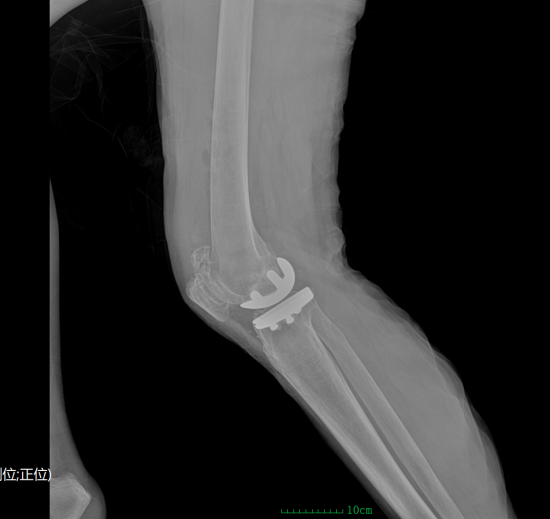

(术前)(术后)

面对手术,家属既期待又担忧。吴院长团队进行了多轮术前评估与讨论,量身制定了单髁置换方案,并耐心解释:“这就像补牙,哪里坏了补哪里,不需要全部更换。”该术式仅置换病变间室,最大程度保留正常结构,具有创伤小、出血少、恢复快的显著优势,尤其适合高龄患者。这一番细致讲解,逐步打消了家属的顾虑,也让他们重新燃起了信心。手术当天,吴院长主刀,通过约6–8厘米微创切口精准完成置换,手术过程顺利、出血极少,展现出高超的技术水平。

术后恢复效果令人惊喜。术后第二天,程奶奶便成功下床行走,疼痛明显缓解,轻松感久违而来。复查显示假体位置理想、力线恢复正常。随着康复推进,她逐渐恢复自主行走能力,上下楼也愈发稳健。病房里重新响起爽朗的笑声,每次查房,她都会竖起大拇指连连称赞。对吴院长及医护团队的由衷感谢,既是对医疗技术的高度认可,更是对医者仁心最真挚的回应。